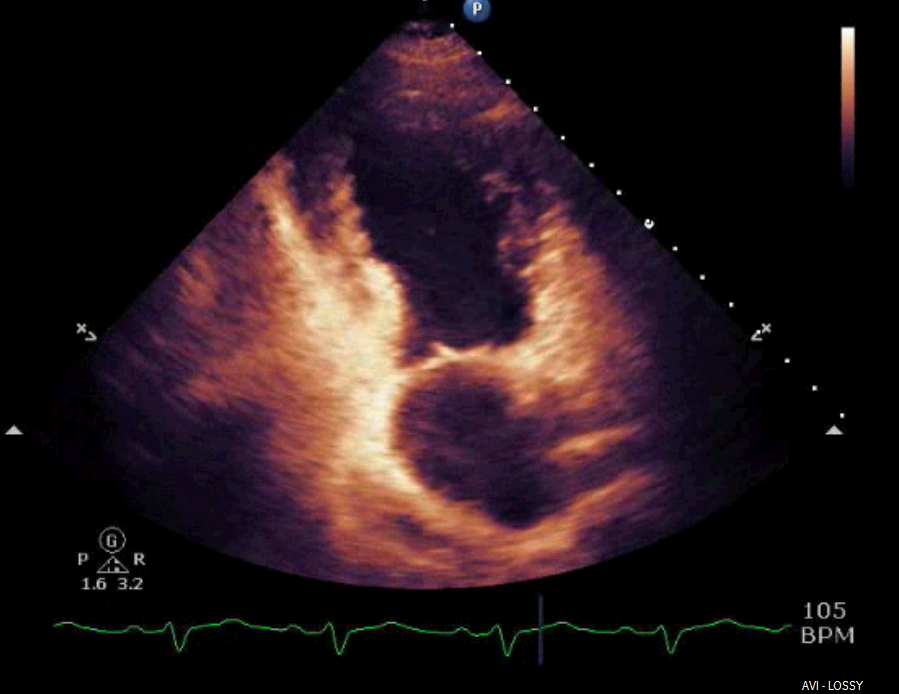

Neurogenic stunned myocardium is a triad of reversible left ventricular dysfunction, electrocardiogram changes and elevation of cardiac enzymes. Clinically, this provides diagnostic challenges in the setting of subarachnoid hemorrhage (SAH) due to the diagnostic uncertainty. The pathophysiological mechanisms for neurogenic stunned myocardium have included hypothalamic and myocardial perivascular lesions. More recently, alternative research has focused on myocardial microvascular dysfunction and genetic polymorphisms. Management has remained largely supportive with case reports citing the benefits of inotropes and intra-aortic balloon pumps in the setting of cardiogenic shock complicating NSM. When NSM follows SAH there are numerous complications, including pulmonary edema, arrhythmias and prolonged intubation, which can impact outcomes and increase morbidity and mortality. This highlights the need for accurate and timely diagnosis of NSM which has remained a clinical challenge. We report a case of a 52-year-old patient who presented to the ICU with complaints of atypical chest pain without neurologic complaints or lateralizing symptoms. She was admitted to the ICU for ongoing chest pain with concurrent ECG T-wave inversions. Within 24 hours she developed lateralizing neurologic signs and altered mental status with subsequent imaging revealing evidence of a SAH. We describe characteristics and outcomes of NSM in this patient with aneurysmal associated SAH.References